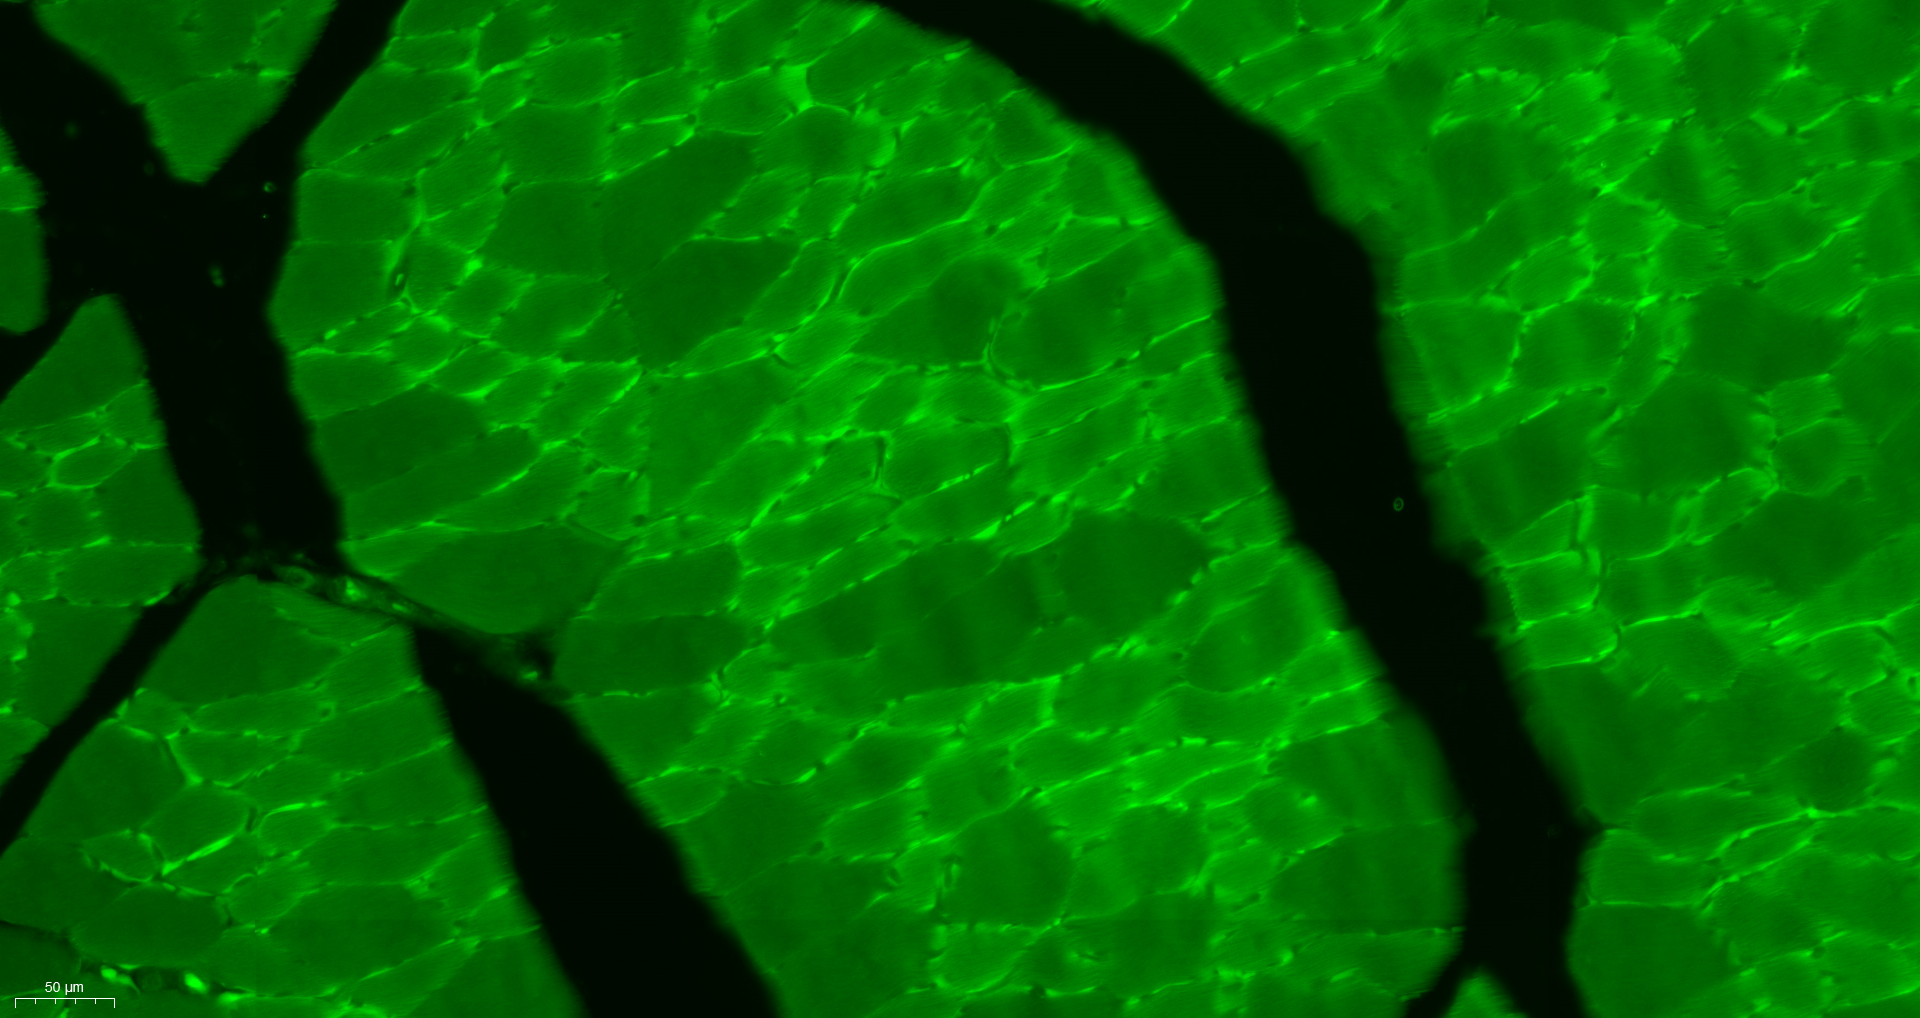

Immunohistochemistry analysis in human skeletal muscle and liver tissues using HPA040066 antibody. Corresponding SYNM RNA-seq data are presented for the same tissues.

TargetSYNM

- Target descriptionsynemin